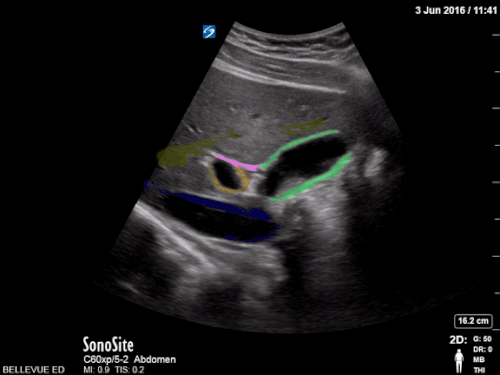

Name the yellow structure

What is portal vein

Name the structure A

What is CBD (common bile duct)

bonus point 100: what is the normal measurement of the CBD